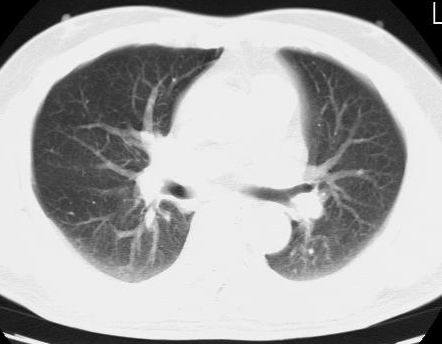

标题: CT15869:男性,71岁,因咳嗽而就诊,请讨论右上肺病变性质 [打印本页]

标题: CT15869:男性,71岁,因咳嗽而就诊,请讨论右上肺病变性质

患者,男性,71岁,因咳嗽而就诊,

典型的右肺中心性肺癌并纵隔淋巴结转移

右肺中心性肺癌并纵隔淋巴结转移可能性大!

考虑右肺中心性肺癌并右肺门及纵隔淋巴结转移。

1,右肺中心型ca,气管隆突旁淋巴结转移。

2,右膈明显抬高,建议肝脏扫描排除转移或原发灶。